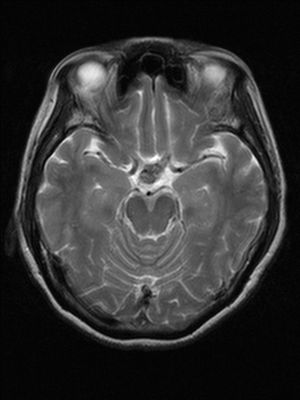

A 55-year-old female presented with a one-month history of excessive thirst and polyuria. She had an operation for adenocarcinoma of the lung about 21 months ago.